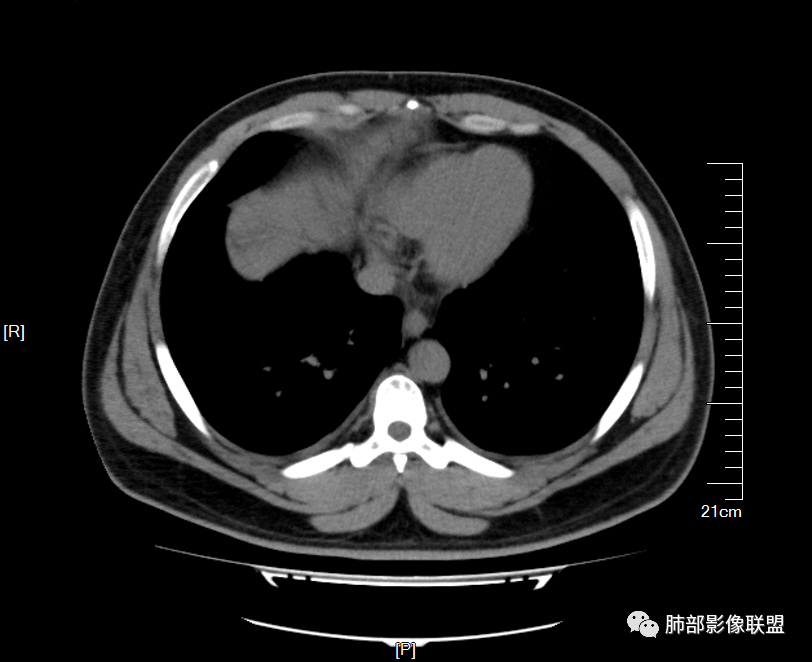

【每日晨读】 双肺满布磨玻璃结节,原来如此!

双肺多发弥漫性磨玻璃结节影,大小不一,形态不规则,部分融合,支气管未见明显扩张,部分血管束略增粗,叶裂胸膜增厚,临床有痛风,左足痛6天,考虑:1:痛风结节(一般实性结节,很少磨玻璃结节影)2:血管炎?3:病毒性肺炎(水痘-疱疹肺炎?)

双肺多发腺泡结节及磨玻璃,小叶间隔增厚(大网格状),腺泡结节内及磨玻璃内可见细网格影(小叶内间隔增厚),影像表现符合肺泡出血改变,血肌酐升高,考虑肺肾综合征。鉴别肺水肿。

两肺弥漫向心分布的腺泡结节,部分融合,两肺小叶间隔增厚,血肌肝高,考虑肺泡性肺水肿

青年男性,痛风、肾功能不全病史,双肺多发结节状、斑片状阴影,支气管血管束增粗,可见支气管袖口征,叶间裂及小叶间隔增厚,考虑肺水肿。

年轻男性,既往血肌酐升高,左足痛六天入院,有痛风及高血压病史。CT示双肺多发磨玻璃结节影,不规则,部分融合成团或片状,小叶间隔增厚,以双下肺为明显,叶间胸膜亦见增厚。考虑为1.Good-Pasture综合征。2.病毒性肺炎?3.肺水肿?

男32岁。既往曾发现血肌酐升高.此次因左足痛6天入院。有痛风、高血压病史。两肺弥漫性的病变,小片状或者结节状为主病变,小叶中心分部为主,边界不清。心影比较饱满,肝实质密度均匀的降低。考虑为肝损害的影像学改变。综合考虑多功能脏器的损害,肺部损害肺泡炎?肺水肿?或病毒性的肺炎?

年轻男性,有痛风、高血压病史,有肾功不全史。双肺弥漫性分布磨玻璃样结节,部分融合,无重力分布,考虑1.血管炎。2.肺肾综合征。3.肺水肿。

年轻男性,痛风史,高血压史,肌酐高,左足痛6天入院。胸CT:双肺多发弥漫性磨玻璃结节影,大小不一,部分融合,上中下肺都有,中内带多,胸膜下少。部分血管束略增粗,小叶内间隔、小叶间隔增厚,下肺明显,左室大。叶裂胸膜增厚。临床有痛风,左足痛6天,考虑:心衰、间质性肺水肿?弥漫性肺泡出血?鉴别:MPA,肺肾综合征,痛风结节等。

年轻男性,痛风,肌酐高,提示肾功能有损,两肺多发磨玻璃腺泡结节,小叶间隔增厚,双侧少许胸水,血管增粗,考虑肾性肺水肿,DAD,鉴别肺肾综合征,需要更多临床资料

32岁男性,左足痛入院。有痛风、肌酐升高、高血压病史。CT:两肺弥漫磨玻璃结节,小叶间隔增厚、小叶内间质增厚,两侧少量胸水。考虑:1.肺水肿;2.过敏性肺炎;3.肿瘤?

青年男性,双肺多发大小不等斑片状磨玻璃密度影,内见细网格影,并可见小叶间隔增厚,双侧胸腔少量积液,患者曾有血肌酐增高,提示曾有肾损害,并有痛风、高血压病史,考虑肺肾综合征,鉴别过敏性肺炎